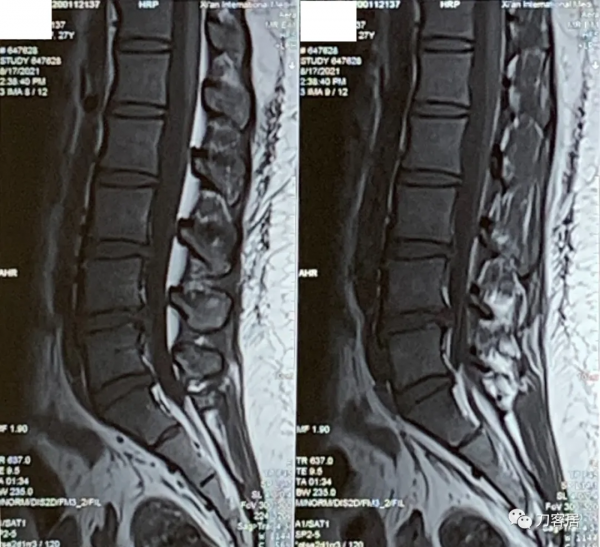

圖2. 20210817術前腰椎MRI矢狀面T2相,提示腰4-5,腰5骶1椎間盤突出,腰4-5椎間盤應該脫落進入椎管內,腰5椎體後緣了。

圖3. 20210817術前腰椎MRI矢狀面T2相,提示腰3-4-5-骶1椎間盤突出,腰3-4很輕,無需處理,腰4-5突出較大。

圖4. 20210817術前腰椎MRI矢狀面T1相,提示腰3-骶1椎間盤突出,腰4-5較大。